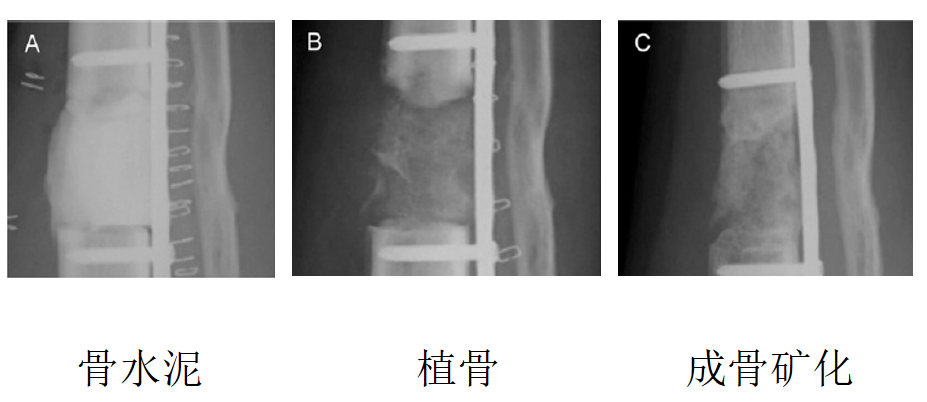

成骨机制

究竟发生了什么?我们还能够做什么?植骨的准确节点如何把握?

人类活体标本实验

N=14骨缺损大于5cm实施Masquelet技术观察病理切片、诱导膜上培养骨髓干细胞检测ALP活性、PCR分析IL-6、VEGF、Col-1基因表达

微观异物炎症反应----巨噬细胞出现越靠近骨髓腔,炎症反应越明显

富血管化炎症诱导膜内形成血管内皮细胞富血管化是肉芽组织形成的关键

时限变化成熟纤维组织形成血管微循环明显减少------老化

膜内成骨StageII 植骨后出现软骨内成骨与膜内成骨并存,以膜内成骨为主

诱导成骨分泌成骨因子直接影响微血管再生长和成骨效能

成骨活性一个月成骨活性最显著Stage II 植骨的最佳时机